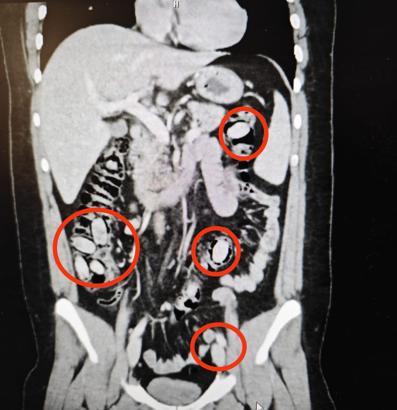

Eskişehir Emniyet Müdürlüğü ekipleri, yurtdışından Eskişehir’e geldiği belirlenen S.A.’yı kent girişinde durdurdu. Sürekli midesini tutmasından şüphe edilmesi üzerine S.A., hastanede sağlık kontrolünden geçirildi. Şüpheli S.A.’nın hastanede çekilen röntgeninde midesinde 44 kapsül olduğu tespit edildi. Eskişehir Cumhuriyet Başsavcılığı’nın talimatıyla cerrahi müdahaleye alınan S.A.’nın midesindeki 44 kapsül çıkarıldı. Kapsüllerde yapılan incelemede içerisinde uyuşturucu metamfetamin (bonzai) maddesi olduğu belirlendi.